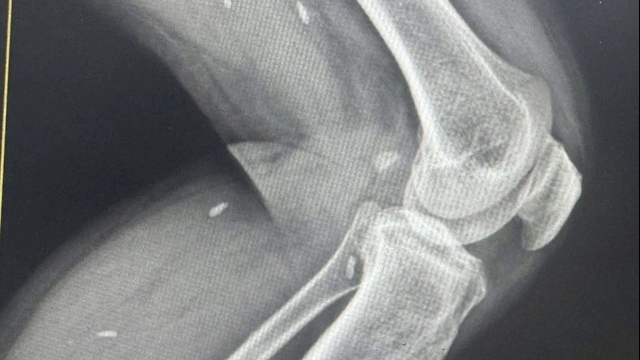

| Ảnh minh hoạ |